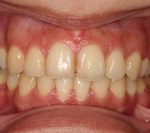

矯正の症例

1) 矯正前の状態

叢生(そうせい…歯がデコボコしたり、重なりあって生えていたりする状態)

開咬(かいこう…奥歯はしっかり噛んでいるが、上下の前歯が噛まずに隙間がある状態)